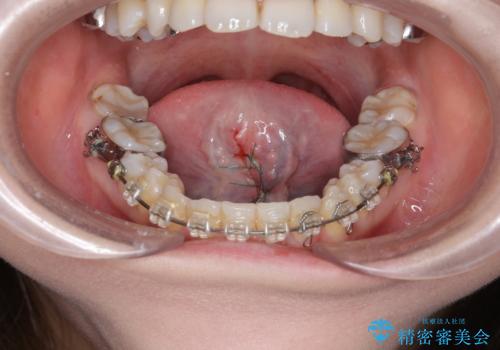

滑舌を改善! 舌小帯の形成術

- 他院での矯正治療中、滑舌の改善を求めて来院されました。

10分程度の短時間で終わる、舌小帯の形成術を行い滑舌の改善を計画します。

術後すぐに、ら行さ行の発音がしやすくなった!と喜んでいただくことができました。